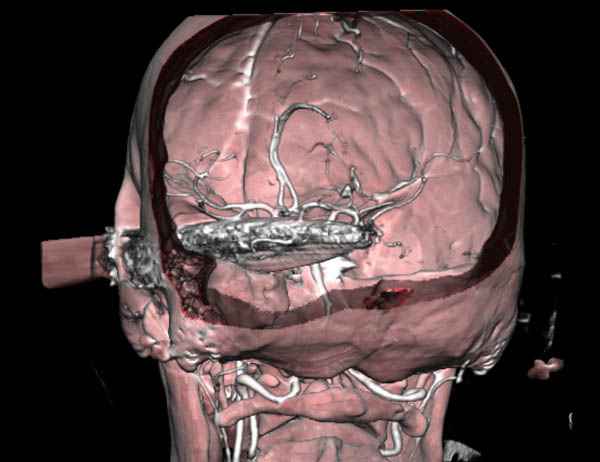

В своих выступлениях я рассказывал, что наши центры в мирное время по пенетрирующим травмам не уступает Ираку или Афганстану, и вот недавно к нам поступила больная 22 лет, травма "ножом в глаз" от бывшей подруги нынешнего "бой френда".

При поступлении в сознании, жаловалась на неприятные ощущения в глазнице.

По протоколу сделаны все необходимые исследования: рентген, ангиограмма с 3Д реконструкцией, где обнаружили что все жизненно важные сосуды не задеты, даже некоторые "сидят" изгибаясь на ноже.

Одним махом нож удалить не удалось, пришлось раскачать и потом двумя руками удалили нож. Рана без кровотечения, обработана и зашита.